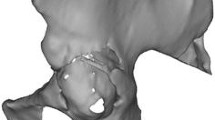

The rotational center of the defective acetabulum had to be confirmed before cage design. This required drawing a single plane containing three points: the mid-point of the line connecting the anterosuperior iliac spines, that of the pubic symphysis, and that of the fifth lumbar vertebra. Then, a line perpendicular to the plane was drawn starting from the geometric center of the contralateral femoral head and extended isometrically, allowing for identification of the center of the diseased femoral head, which theoretically should correspond to the center of the ipsilateral femoral head (Fig. 1).

The method for determining the rotational center of a severely defective acetabulum is shown. A single plane is drawn containing three points: the mid-point of the line connecting the anterosuperior iliac spines, the center of the pubic symphysis, and the mid-point of the fifth lumbar vertebra. Then, a line perpendicular to the plane is drawn starting from the geometric center of the healthy femoral head and extended isometrically, allowing identification of the center of the diseased femoral head.